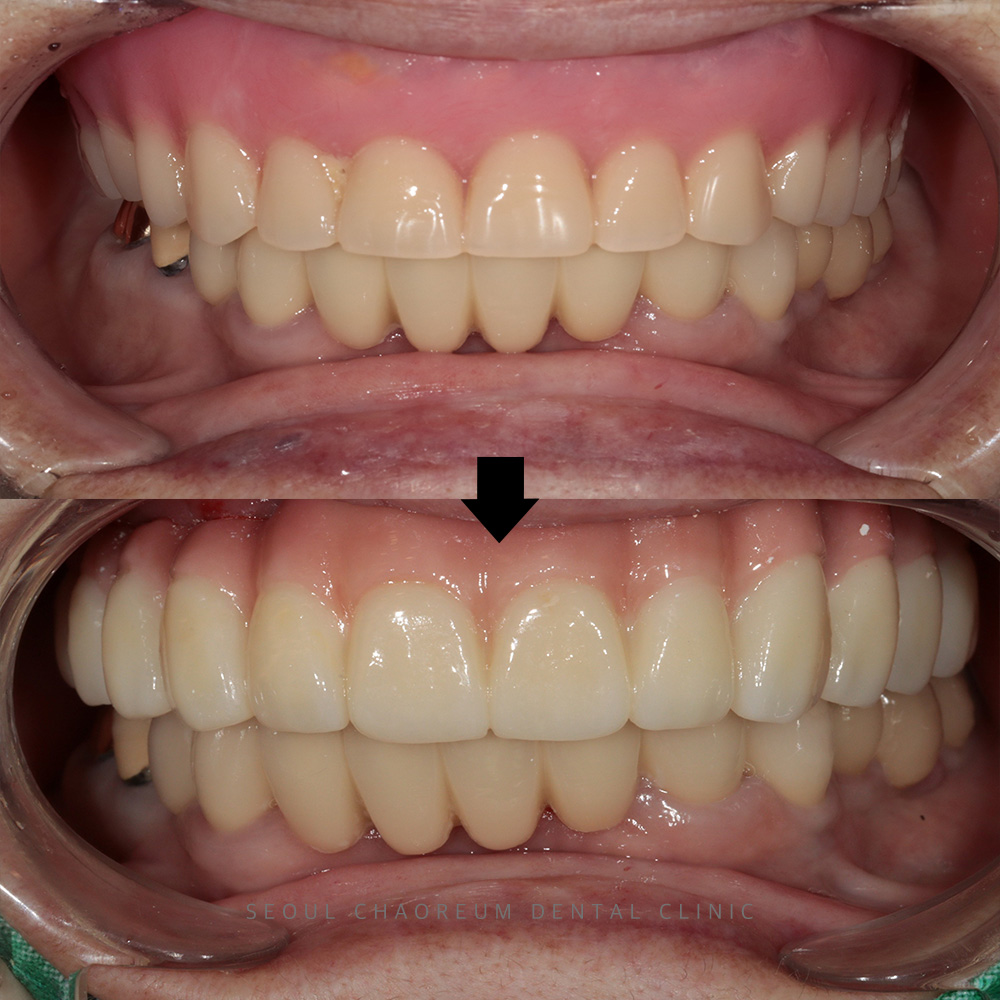

병점치과 위 앞니 상담 원해요 앞니는 말할 때나 웃을 때 가장 먼저 보이는 부위인 만큼, 기능뿐 아니라 심미적인 역할도 매우 큽니다. 과거에는 앞니가 손상되었을 때 브릿지 치료를 선택하는…